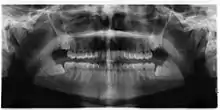

Coronectomy of impacted wisdom tooth post-op xray showing root remnants (red arrow) and inferior alveolar nerve (green arrow)

Coronectomy is a procedure where the crown of the impacted wisdom tooth is removed, but the roots are intentionally left in place. It is indicated when there is no disease of the dental pulp or infection around the crown of the tooth, and there is a high risk of inferior alveolar nerve injury.[31]

Coronectomy, while lessening the immediate risk to the inferior alveolar nerve function has its own complication rates and can result in repeated surgeries. Between 2.3% and 38.3% of roots loosen during the procedure and need to be removed and up to 4.9% of cases require reoperation due to persistent pain, root exposure or persistent infection. The roots have also been reported to migrate in 13.2% to 85.9% of cases.[31]